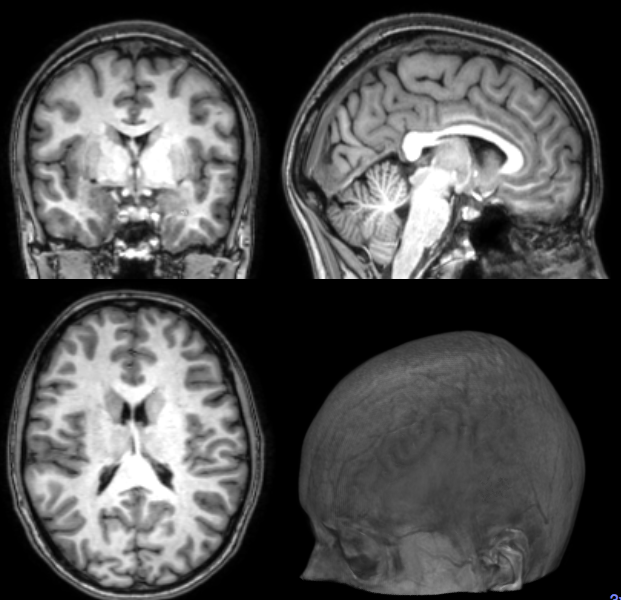

1. Registration (rigid, affine, nonlinear)

3. Segmentation (Manual, Template-based)

Segmentation

Cortical Thickness Estimation